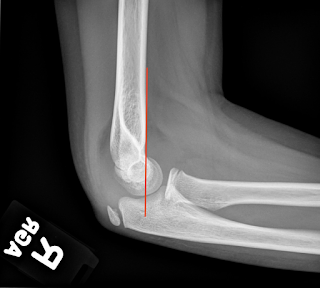

In adults, this most commonly indicates a radial head fracture, but in children, it is most commonly a supracondylar fracture. At this point, looking at the alignment allows you to evaluate for a supracondylar fracture using the anterior humeral line. The anterior humeral line should cross through the middle third of the capitellum. In this case, you can see that the anterior humeral line is normal.

| AHL - through the anterior third of the capitellum |